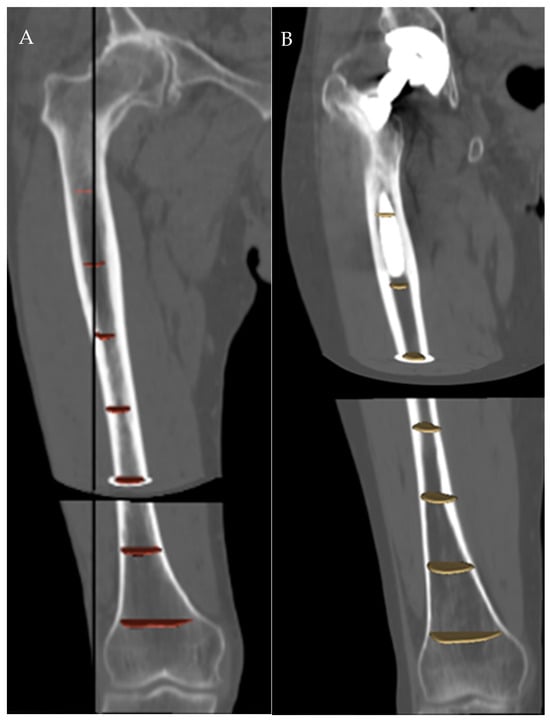

Figure 3. Segmentation of the femoral canal in a native (A) and a prosthetic (B) femur.

It is known from geometry that only one circle passes through three non-aligned points, so for the distal third of the femur, we used the centroids of the slices at 5 (point 1), 10 (point 2) and 15 (point 3) cm above the reference axial plane; for the middle third, those at 15, 20 and 25 cm; and for the proximal third, those at 25, 30 and 35 cm, respectively. For the whole femur, centroids at 5, 20, and 35 cm were used. (Figure 3).

The radius of curvature was calculated at three levels of the femur, namely 10 (distal), 20 (middle) and 30 (proximal) cm above the reference axial plane, as well as for the whole femur. To measure the center of the medullary canal at each level, the level tracing method was used on the inner side of the medullary canal, with possible manual cleaning. Canal centroid was calculated as the geometric center of the level segmentation (Figure 2) using Matlab® (version R2019b, The MathWorks Inc, Natick, MA, USA).